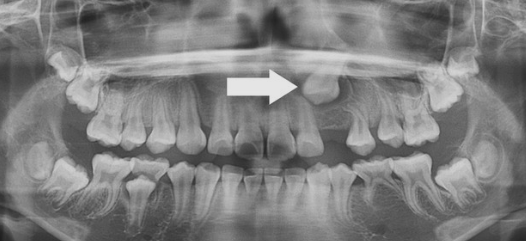

2. 이소 맹출

- 치아의 크기 등 여러가지 원인에 의해 치아가 비정상적인 위치로 자리 잡는 경우를 말합니다. 주로 큰 어금니, 아랫옆앞니, 윗송곳니에서 발생합니다.